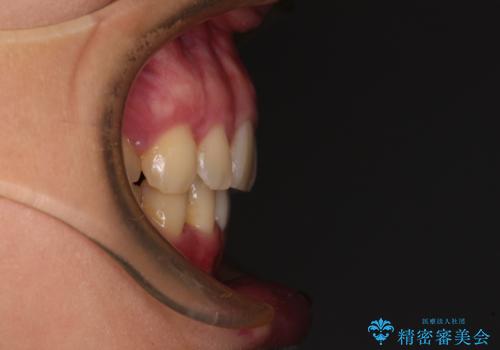

上顎前突 目立たないワイヤー装置での抜歯矯正

- 口元の突出感改善を希望して来院された患者様です。

口元を積極的に引っ込めるために、上下左右の小臼歯計4本を抜歯することとしました。

咬み合わせが深いため、咬み合わせの高さを向上させながら口元を下げることとしました。

左右ともに下顎に対して上顎歯列が前方位にある上顎前突であったので、上顎歯列全体を後方に移動させることで上下咬み合わせを改善し、その上で抜歯矯正により口元の突出感を改善させていきました。